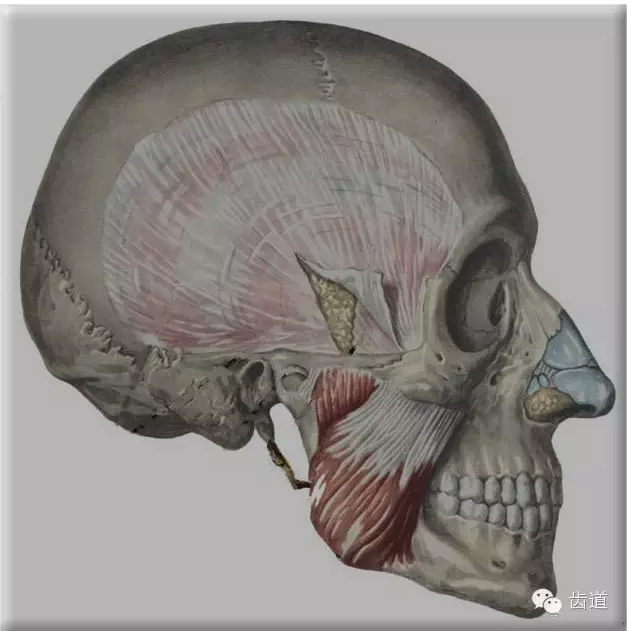

咀嚼肌

咬肌

翼內(nèi)肌

翼外肌

顳肌

舌骨上肌群